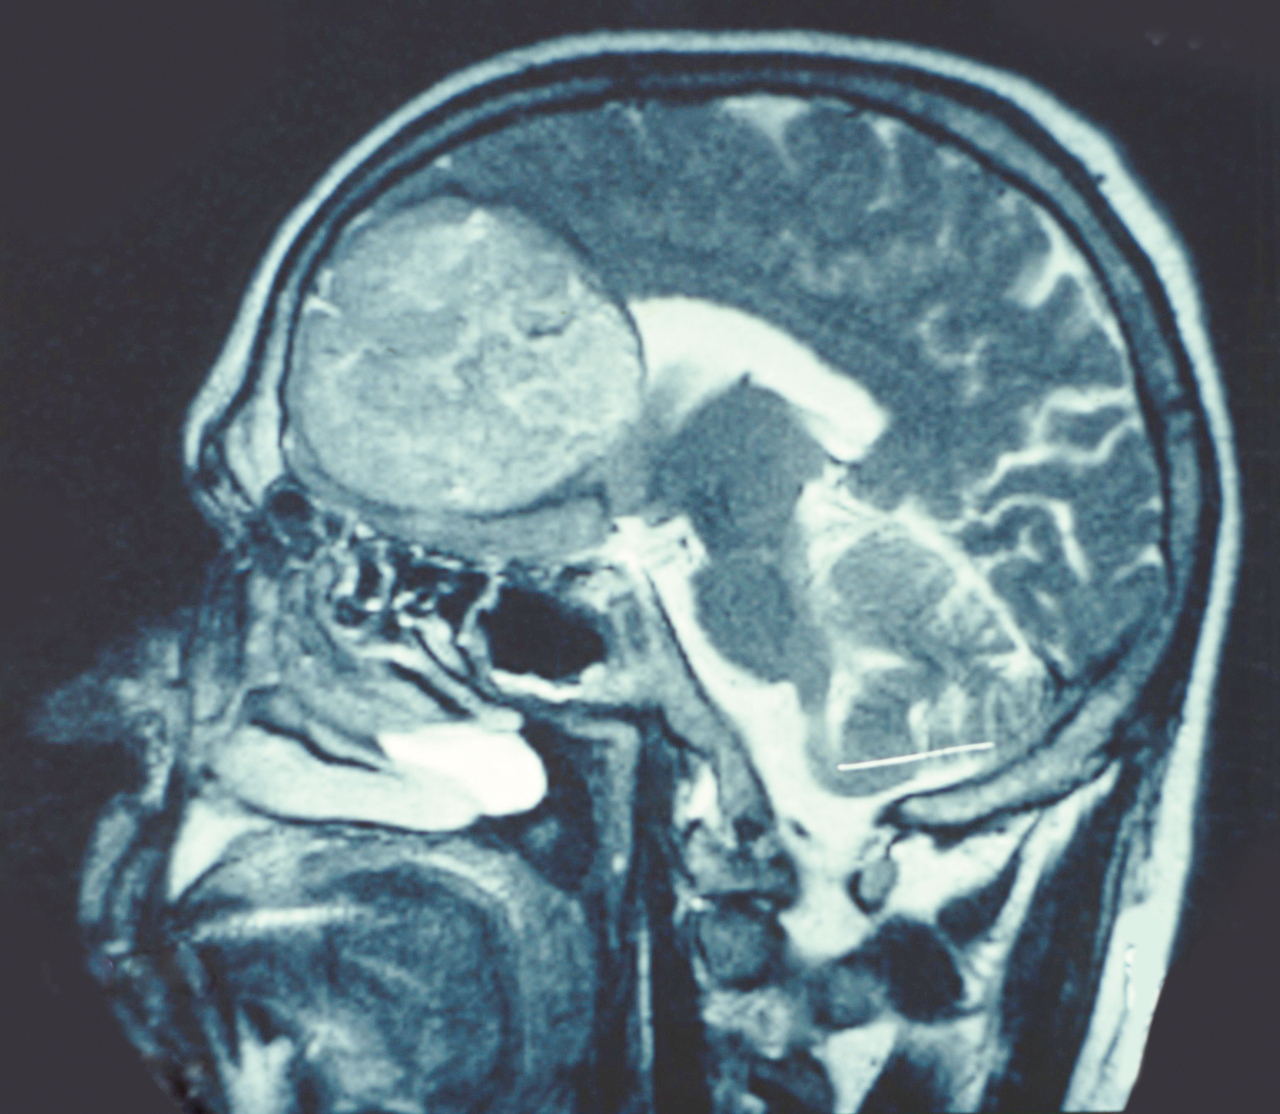

Quel est votre diagnostic ?

Il s'agit de l’aspect IRM en coupe sagittale d’un oligodendrogliome. Les gliomes sont les tumeurs les plus fréquentes du système nerveux central. Les gliomes sont classés en fonction des types cellulaires dont on suppose qu’ils sont issus : les astrocytes et les oligodendrocytes. Les manifestations cliniques inaugurales des tumeurs cérébrales sont dues à leur croissance et résultent de mécanismes différents pouvant coexister selon la nature, la localisation et la vitesse de croissance de la tumeur ainsi que la capacité à générer un œdème péritumoral et une hémorragie intratumorale. Alors que les tumeurs "bénignes", quand elles sont corticales, sont souvent révélées par une épilepsie ou de découverte fortuite, l’apparition d’un déficit doit faire craindre une transformation anaplasique.